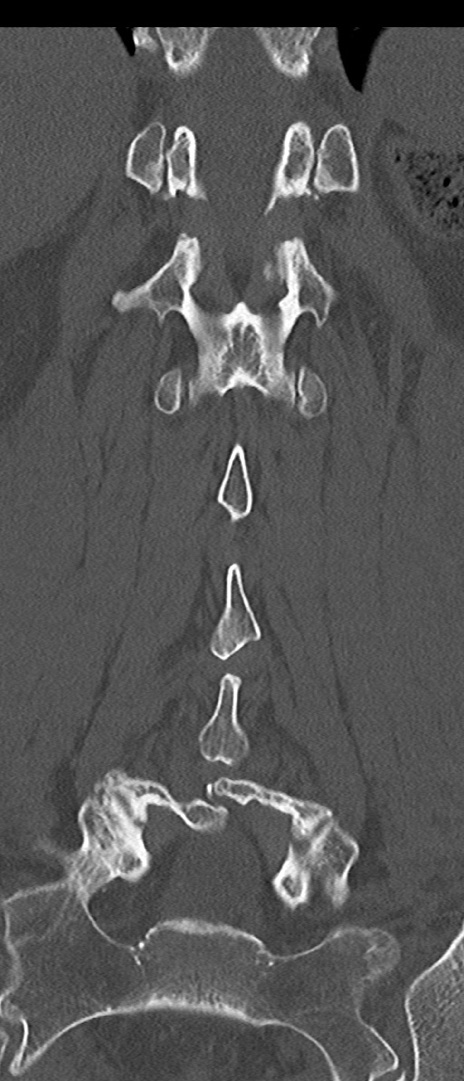

腰椎CT

矢状断像